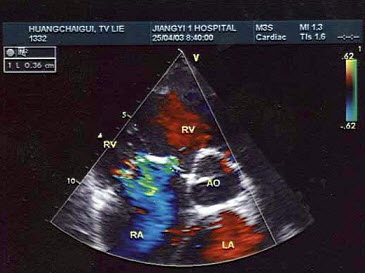

8、单项选择题

该切面未显示法洛四联症哪一症()

A.主动脉骑跨

B.室间隔缺损

C.肺动脉狭窄

D.右室肥厚

E.左心缩小